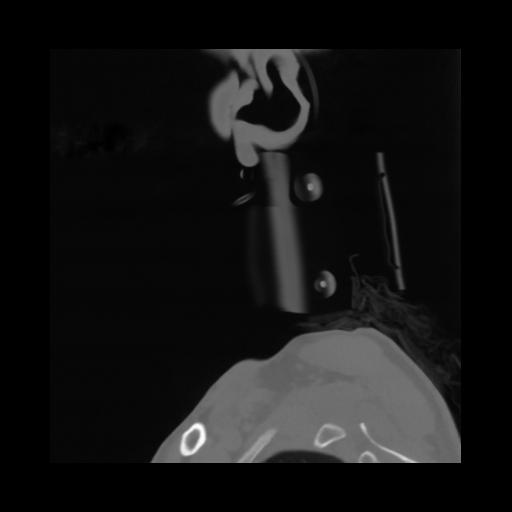

14 P.BLANDAS,,Sagittal,2.000,P.BLANDAS,Sagittal,